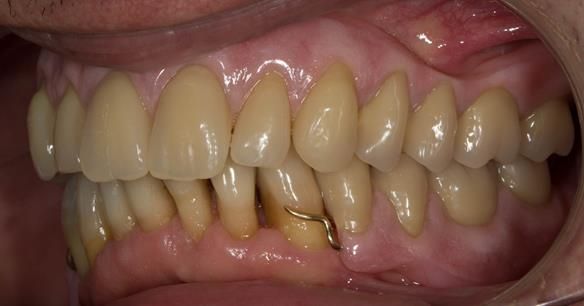

- Definitive dentures (Mk 2) – complete upper metal reinforced and lower cobalt chromium based partial of hygienic Scandinavian design to be made 9 - 12 months after extractions of all upper teeth and LR5 and LL4

The clinical situation and treatment process is shown in detail below with photographs.

The patient has been successfully rehabilitated and is now having periodontal maintenance from Syed Abad, Specialist in Periodontics at the practice. His quality of life has improved considerably. The clinical prosthodontics was provided by me and the technical work by Rowan.